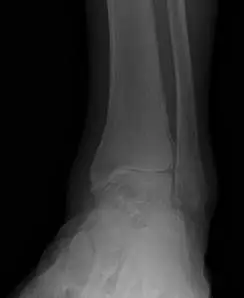

Ankle joint replacements are a reserved procedure for patients who meet certain criteria for functionality involving age, medical conditions, level of arthritis, and activity level, amongst others. The level of arthritis is typically severe and dibilitating as demonstrated in the x-ray image below. This person had a severe ankle fracture many years ago that was surgically repaired and later developed limiting arthritis to the point where they could no longer use their ankle because of pain. There is absence of joint space at the ankle joint along with remodeling of the bones around the ankle due to degeneration of the joint. The abnormal appearance of the thin bone called the fibula is a result of not fixing this bone when the patient had the original surgery.  This is referred to as malunion.

These are pics of the fusion prior to takedown